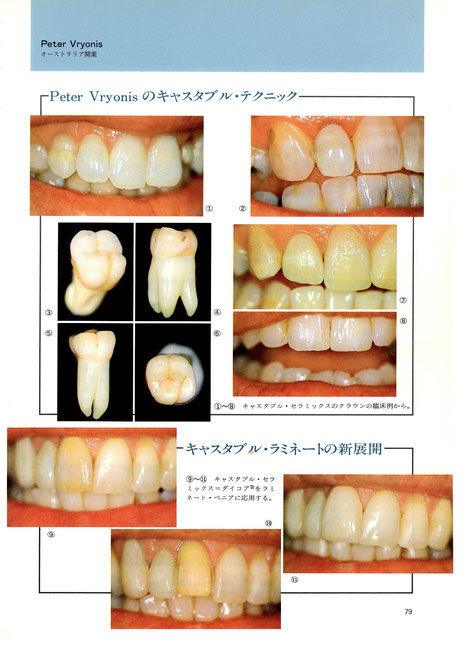

キャスタブル・ラミネートの新展開

キャスタブル・セラミックス=ダイコア ®️をラミネートベニアに応用する。